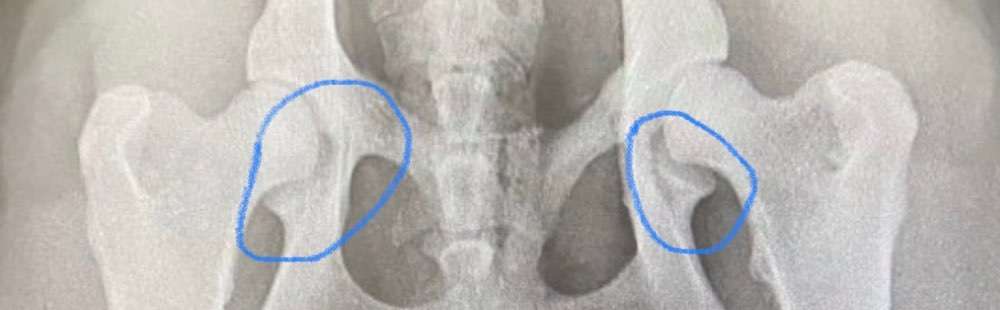

Das war die Röntgenaufnahme von Puma

Ich hab mal ne Frage an diejenigen, die mehr Ahnung von Röntgenaufnahmen haben. Hier sieht man so nen komischen Schatten an der rechten Seite - kommt das auch nur von der Fehllagerung? Ist mir so noch nie aufgefallen (hab aber auch wenig Plan davon)

Bezieht mich auf den Schatten I’m rechten Kreis. Der geht leicht gebogen hinunter

Das dachte ich auch das sieht alles nicht einwandfrei aus ich habe aber dazu was nicht stimmt nicht so viel ahnung die seiten sind auch nicht gleich auch die Köpfe und Pfannen sind unterschiedlich ausgebildet

Villt täuscht das ja auch nur wegen der Lagerung🤔